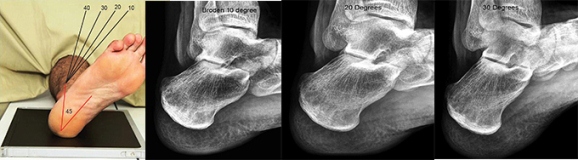

Рентген помогает определить не только наличие шпоры, но и возможные осложнения, такие как трещины или воспаления в тканях.